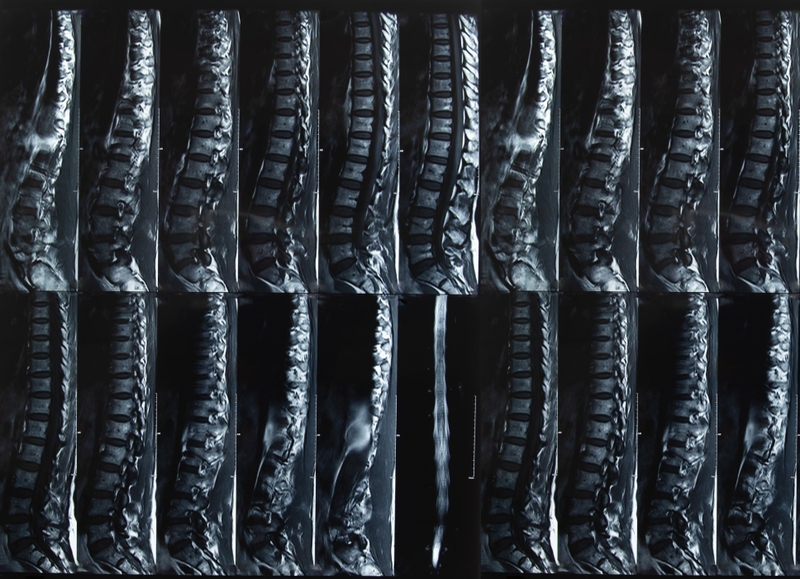

Trong số các kỹ thuật chẩn đoán hình ảnh, chụp X-quang cột sống thắt lưng đóng vai trò quan trọng trong chẩn đoán rất nhiều bệnh lý thường gặp ở cột sống như: Thoái hóa cột sống, dị dạng cột sống, chấn thương cột sống, lao cột sống, thoát vị đĩa đệm, viêm cột sống dính khớp, u tủy sống…

Chụp X-quang cột sống thắt lưng là một trong những kỹ thuật chụp X-quang. Nó được tiến hành tại vùng cột sống thắt lưng của bệnh nhân. Chụp X-quang là kỹ thuật chẩn đoán hình ảnh rất quan trọng được áp dụng từ rất lâu trên thế giới. Rất nhiều bệnh nhân đã được chẩn đoán chính xác, từ đó có phương pháp điều trị hiệu quả nhờ phương pháp này. Chụp X-quang cũng đóng vai trò quan trọng trong nhiều phát minh y học và luôn được ngành y tế toàn cầu đánh giá cao.

Chụp X-quang có thể áp dụng với nhiều vị trí trên cơ thể, trong đó có cột sống thắt lưng. X-quang cột sống thắt lưng được thực hiện khi bạn bị chấn thương hoặc tê bì dai dẳng, đau âm ỉ nhiều ngày. Thông qua hình ảnh chụp X-quang, bác sĩ sẽ đánh giá tổn thương ở các thân đốt sống khi bị chấn thương hay thoái hóa vùng cột sống thắt lưng.

Chụp X-quang cột sống thắt lưng giúp phát hiện nhiều bệnh lý với những mức độ nghiêm trọng khác nhau ở khu vực cột sống thắt lưng của người bệnh.

Chụp X-quang cột sống thắt lưng có ý nghĩa quan trọng trong chẩn đoán nhiều bệnh lý, đặc biệt là các bệnh liên quan đến cơ xương khớp. Ưu điểm của phương pháp này là dễ thực hiện, cho kết quả tương đối chính xác chỉ trong thời gian ngắn với chi phí thấp. Bài viết đã mang đến cho người đọc thông tin cơ bản về kỹ thuật này và những bệnh lý có thể phát hiện được thông qua chụp X-quang tại cột sống thắt lưng.